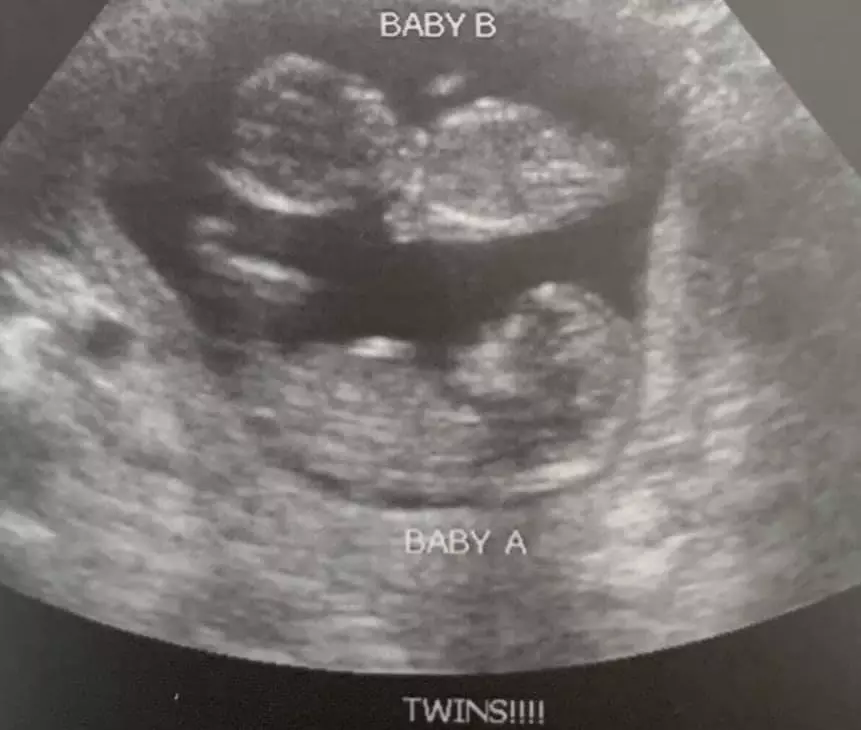

Displaying obvious ineptitude from the start, the nation’s largest abortion business only informed the woman she was pregnant with twins after the chemical abortion she’d been given by Planned Parenthood staff failed.

Problem #2: at seven weeks the vast majority of competent sonographers will never miss twins at that point. But women who find out they are having twins are far less likely to abort twins, as the thought of aborting only one baby does t seem quite as bad as aborting two. So....either an incompetent sonographer missed the fact that she had twins or didn’t want to tell her and have her thousand dollars walk out the door with her.

She did the course of the abortion pill and nothing happened. She went back two weeks later and had another ultrasound at approximately nine weeks and they said ‘oh well, it didn’t work, and you are having twins.’ She asked what could be done and they said nothing. She left, found the number to call on google, and that led her to my office.

“These twins have now delivered at term, uncomplicated by any other issues,” Boles wrote in his social media post, “and are at home with their parents, who are exceedingly pleased that a decision made under pressure and while in fear did not work out as planned.”